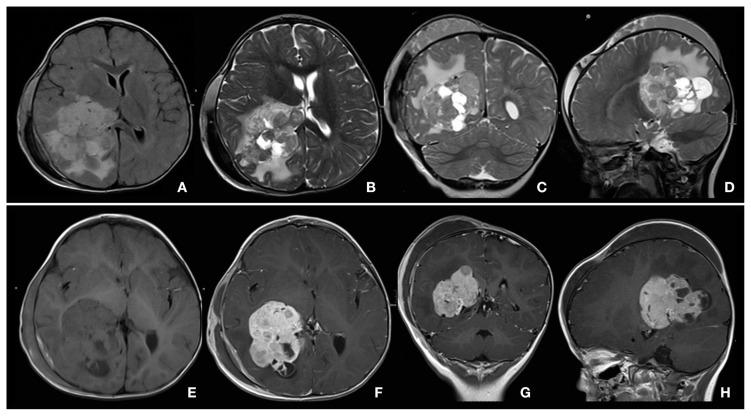

Magnetic resonance imaging (MRI), frequently with contrast enhancement, is the preferred imaging modality for many indications in children. Practice varies widely between centers, reflecting the rapid pace of change and the need for further research. Guide-line changes, for example on contrast-medium choice, require continued practice reappraisal. This article reviews recent developments in pediatric contrast-enhanced MRI and offers recommendations on current best practice. Nine leading pediatric radiologists from internationally recognized radiology centers convened at a consensus meeting in Bordeaux, France, to discuss applications of contrast-enhanced MRI across a range of indications in children. Review of the literature indicated that few published data provide guidance on best practice in pediatric MRI. Discussion among the experts concluded that MRI is preferred over ionizing-radiation modalities for many indications, with advantages in safety and efficacy. Awareness of age-specific adaptations in MRI technique can optimize image quality. Gadolinium-based contrast media are recommended for enhancing imaging quality. The choice of most appropriate contrast medium should be based on criteria of safety, tolerability, and efficacy, characterized in age-specific clinical trials and personal experience.

磁共振成像(MRI),通常需进行对比增强,是儿童多种适应症的首选成像方式。各中心之间的实践差异很大,这反映了变化的快速步伐以及进一步研究的必要性。例如,关于造影剂选择的指南变化需要持续的实践重新评估。本文回顾了儿科对比增强MRI的最新进展,并就当前的最佳实践提出建议。来自国际认可的放射学中心的九位顶尖儿科放射学家在法国波尔多召开了一次共识会议,讨论对比增强MRI在儿童一系列适应症中的应用。文献回顾表明,很少有已发表的数据为儿科MRI的最佳实践提供指导。专家们的讨论得出结论,对于许多适应症,MRI优于电离辐射成像方式,在安全性和有效性方面具有优势。了解MRI技术中针对特定年龄的调整可以优化图像质量。推荐使用钆基造影剂来提高成像质量。最合适的造影剂选择应基于安全性、耐受性和有效性标准,这些标准在特定年龄的临床试验和个人经验中有所体现。